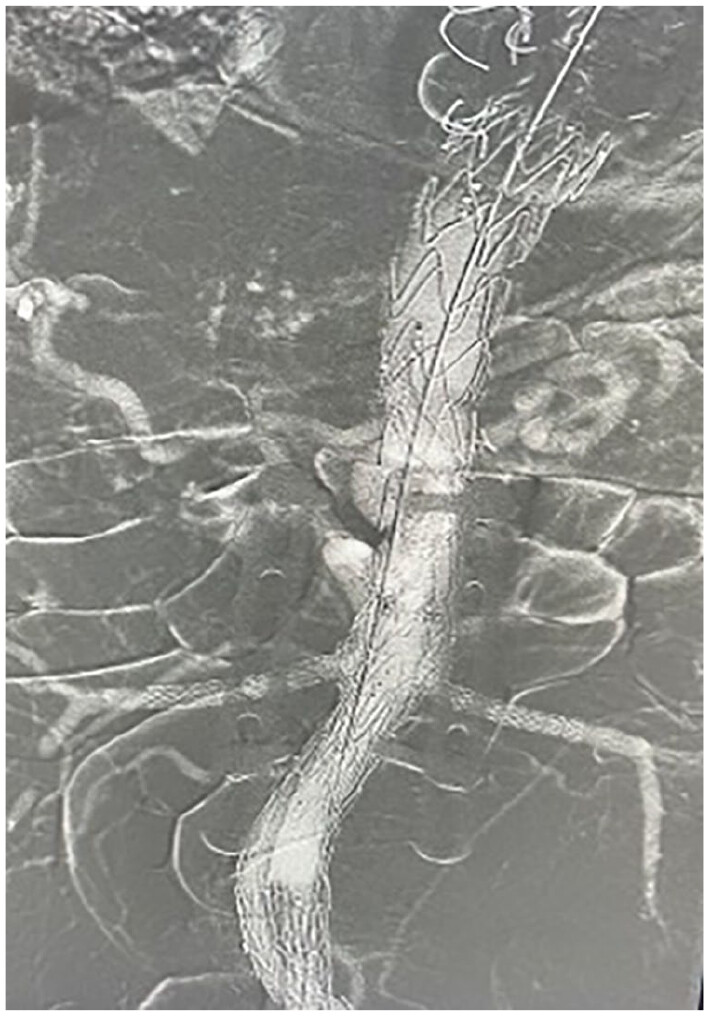

This contrast-free protocol using carbon dioxide angiography for fenestrated/branched endovascular aneurysm repair can reduce the risk of renal damage, facilitating access to F/BEVAR for patients with chronic kidney disease journals.sagepub.com/doi/10.1177/15…